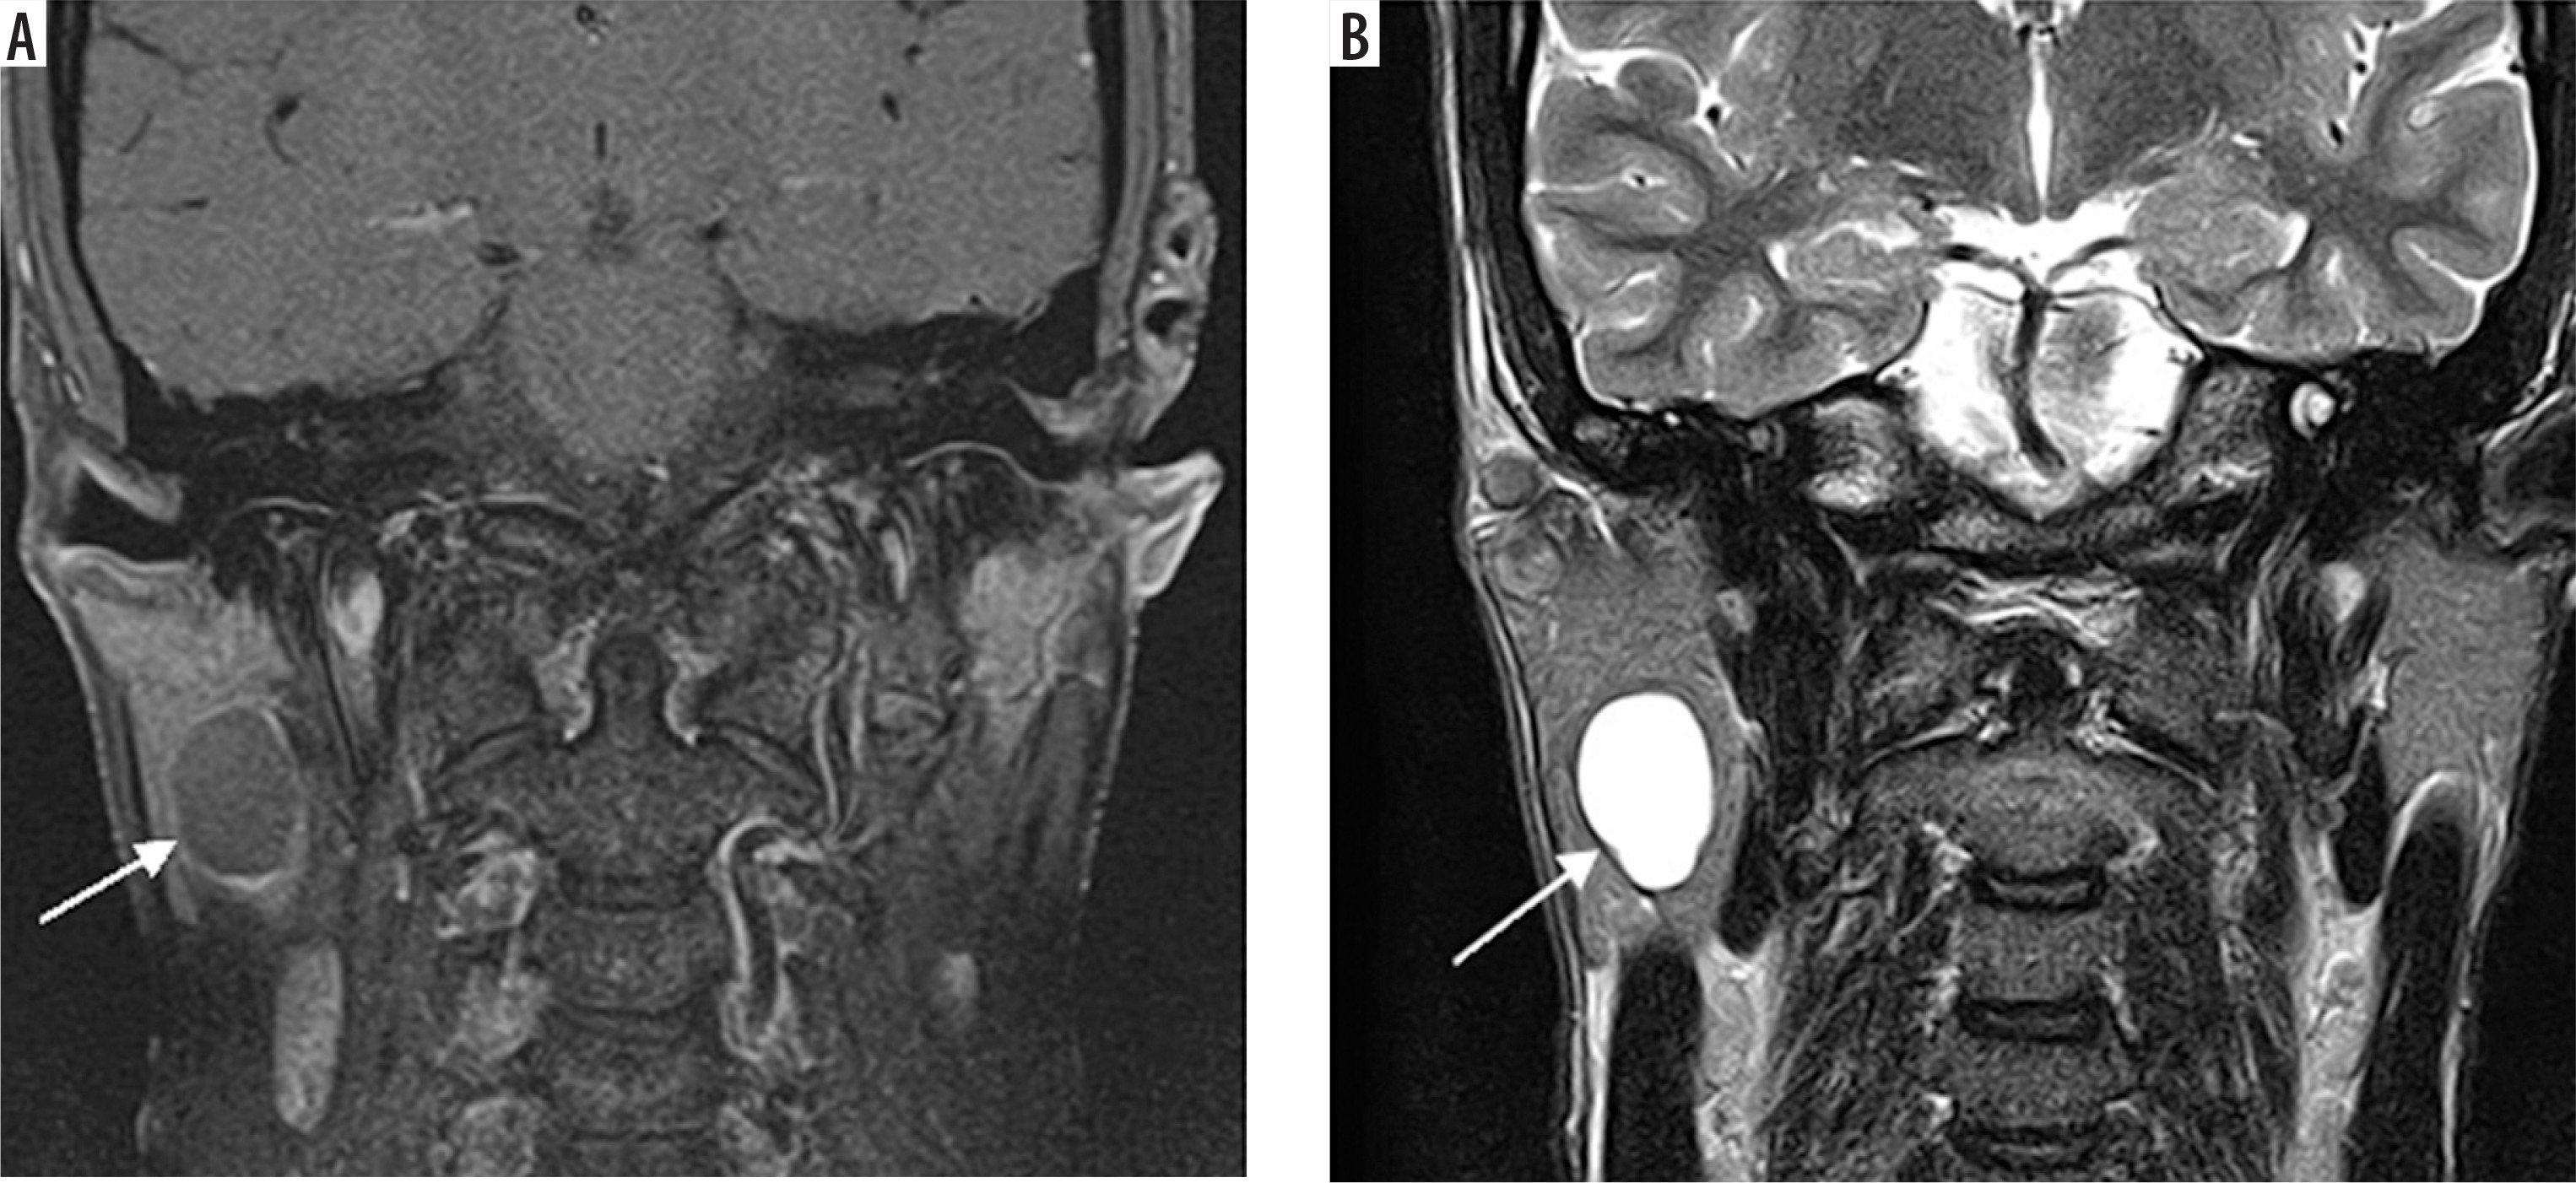

Case 1: Parotid lymphoepithelial cyst

A 30-year-old male patient presented with painless swelling of the right parotid region. Coronal section of MRI shows a right parotid lymphoepithelial cyst. Cystic lesion with water content has low signal intensity on T1-weighted images, hence appears hypointense. In contrast, it has high signal intensity on T2-weighted images and has hyperintense appearance (Figures 4A-C).

Figure 4

Coronal section of MRI of parotid lymphoepithelial cyst. A) T1-weighted MRI image – note the hypointensity of the cyst on right parotid gland. B) T2-weighted MRI image – note the hyperintensity of the cyst. This classic signal pattern helps differentiate cystic lesions from other tumours, highlighting the importance of correlating imaging features with the clinical context for accurate diagnosis and treatment planning [Courtesy: Radiopaedia. DOI: https://doi.org/10.53347/rID-149218, rID:149218]